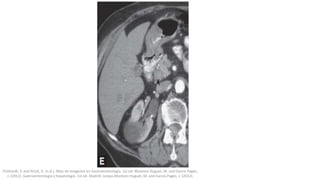

TC abdominal

La TC convencional tiene mayor sensibilidad (70-90%)

pero su disponibilidad es menor y comporta mayor coste

y radiación para el paciente.

La sensibilidad de la detección mediante TC depende de

la composición del cálculo y del grado de dilatación

ductal; la presencia de una semiluna de bilis perfilando

un cálculo en el colédoco suele ser un hallazgo de

utilidad.